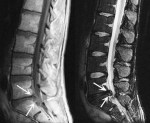

Diagnostics: CT or MRI?

Given the high frequency of spontaneous remission of the clinical or following conservative treatment, in cases where there are no red lights, it is recommended that you wait at least 4-6 weeks after the onset of symptoms before getting medical checkups and diagnostic images. CT and MRI are equivalent in terms of diagnostic accuracy, but MRI has the advantage of not exposing the patient to any radiological risk.

The physicians responsible for the clinical management of the patient must correlate information from the reports of diagnostic imaging with the clinical situation, explaining that the radiological findings of disc protrusion is frequently asymptomatic in the general population.

The use of intravenous contrast agents with CT or MRI is indicated in the diagnosis of lumbar disc hernia in patients already undergoing surgery and only in cases where the study without contrast enhancement has an inconclusive result